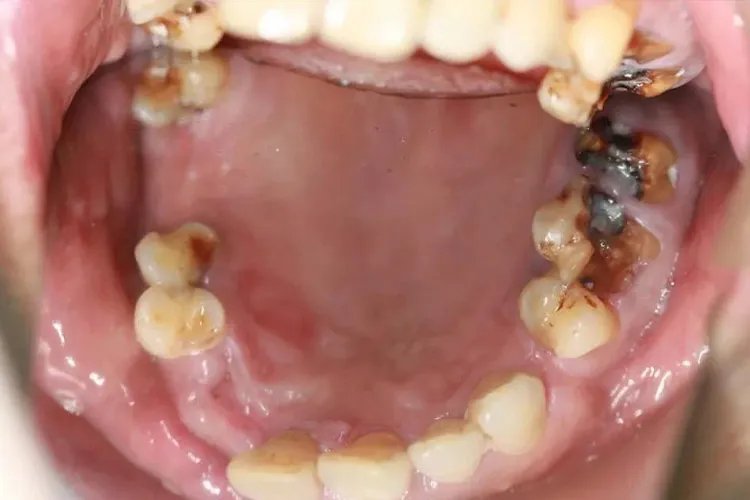

深龋龋坏达牙本质深层,对冷热刺激更为敏感。可见较深的龋洞,位于邻面的龋洞以及隐匿性龋洞,仅能从牙面看到一暗黑色区域,深龋洞口开放时,食物嵌人洞中会引起疼痛。刺激去除后,疼痛可立即消失。

病因龋病是一种多因素疾病,口腔微生物、碳水化合物、敏感的宿主和食物四个因素相互作用的结果。诊断本病可根据视诊和探诊的方法进行诊断。观察牙齿有无颜色变化及龋洞的形成,可用探诊探测龋洞的深度及大小。此外,还可做相关检查,口腔X线检查显示龋坏部位透射影像或边缘模糊,荧光检查显示龋坏部位发出荧光,以帮助诊断。治疗龋齿有化学疗法、再矿化治疗、预防性树脂填充及修复性治疗等方法。化学疗法用化学要药物处理龋损,适用于恒牙早期釉质龋、乳前牙邻面等,常用75%氟化钠甘油糊剂或10%硝酸银和氨硝酸银。再矿化治疗采用人工方法使已脱矿、变软的釉质或牙骨质发生再矿化,可选用含不同比例钙、磷和氟,将浸有再矿化液的棉球置于患处,亦可配成漱口液。预防性树脂填充是指采用窝沟封闭剂防治窝沟龋,适用于窝沟内微小浅龋及可疑龋。修复性治疗根据不同的窝洞选择不同的树脂材料进行填充,常见的有氢氧化钙、玻璃离子粘固剂等。